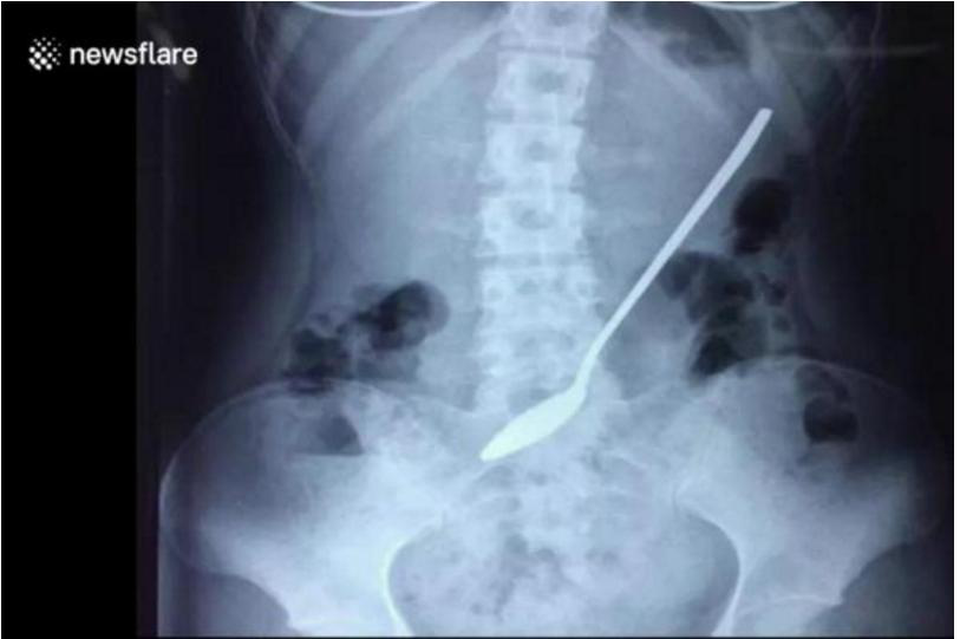

Đoạn phim quay tại bệnh viện ở Yiwu, tỉnh Chiết Giang, Trung Quốc cho thấy các bác sĩ xem xét hình ảnh chụp X-quang xác định chiếc thìa đang nằm bên trong cơ thể nữ sinh viên trước khi tiến hành phẫu thuật để loại bỏ nó.

Chiếc thìa 20 cm bị nuốt vào bụng bệnh nhân và ở đó suốt 3 ngày